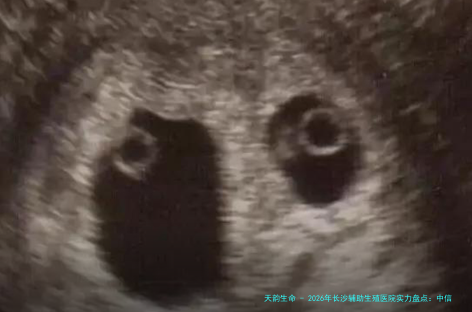

2026年长沙辅助生殖医院实力盘点:中信湘雅、湘雅医院等五家公立机构技术解析附选性别疑问解答

设备以及技术:导入了的胚胎实践室器械,如时差成像培养系统等。在胚胎植入前遗传学检测(PGT,俗名第三代试管婴儿) 领域技术成熟,有经验。

具体讲解:中信湘雅由试管婴儿医生卢光琇教授带头,其科研和临床实力强大,尤其在遗传病截断方向成效显著。医院每一年实现的试管婴儿周期限数位居全国前线,对于有明确遗传性疾病家族历史、需要进行胚胎遗传学诊断的家庭来讲,这里是重要的抉择之一。